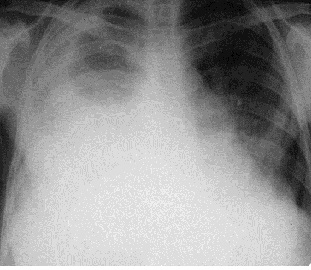

Затемнения могут отображать патологические процессы, поражающие дольку (очаговые тени) (рис. 4), больше чем дольку, но меньше сегмента (фокус затемнения), сегмент или долю (ограниченное затемнение) (рис. 5); большую часть легкого или соответствующей половины грудной клетки (обширное или субтотальное затемнение) (рис. 6). Очаговые тени разделяются на мелкие – до 4 мм в диаметре (поражения ацинуса), средние – 5-10 мм в диаметре (поражения нескольких ацинусов) и большие – 11-15 мм (поражения всей дольки).

Рис. 6. Рентгенограмма органов грудной полости в прямой проекции. Более 2/3 правого легочного поля затемнено. Субтотальное затемнение. Морфологический субстрат – гидроторакс.